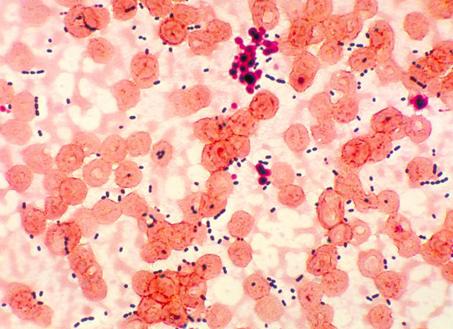

Эти микроорганизмы имеют форму овала и в мазках всегда держатся вместе в скоплении или выстраиваются в цепочку.

• Профилактика

Энтерококки (лат. Enterococcus) – это род шарообразных или слегка вытянутых, грамположительных бактерий семейства Энтерококковые (Enterococcaceae). Размещение обычно происходит парами (диплококки) или же короткими цепочками.

По физиологическим характеристикам энтерококки очень схожи со стрептококками, в связи с чем, изначально, до 1984 года, этот вид бактерий относили к стрептококковой инфекции.

По состоянию на 2017 год, к энтерококкам причислено 15 видов бактерий, наиболее популярными из которых являются – энтерококк фекальный (Enterococcus faecalis) и энтерококк фэциум (Enterococcus faecium), которые также выступают в качестве симбиотических микроорганизмов кишечника человека.

Энтерококки представляют собой круглые или слегка овальные, грамположительные, факультативные анаэробы, размером 0,6–2,0 на 0,6–2,5 мкм, для размножения и жизнедеятельности которых достаточно как большое, так и малое количество кислорода. Рост и развитие этого вида бактерий происходит за счет энергии брожения, при температуре°С. Наиболее же оптимальной температурой окружающей среды для наилучшего размножения инфекции является°С.